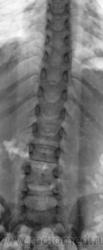

Травма. Ребенок направлен на рентгенографию поясничного отдела позвоночника.

Д12, 1-я ст компрессии....

ТН12, нужно бы сделать и грудной повыше, может быть компрессия нескольких позвонков, и не обязательно подряд.

Сделали и повыше. Нет. Только один. Я просто "боковуху" при обработке обрезал.

Смутило увеличение размеров позвоночного канала в нижнепоясничном отделе - увеличение расстояния между корнями дужек в прямой проекции и вдавленность задних контуров позвонков в боковой. Нет ли у ребенка признаков неврологических расстройств - это может быть опухоль позвоночного канала, я подобное встречал, привожу снимок, тоже думали о переломе тел, здесь конечно все более запущено, чем в Вашем наблюдении...